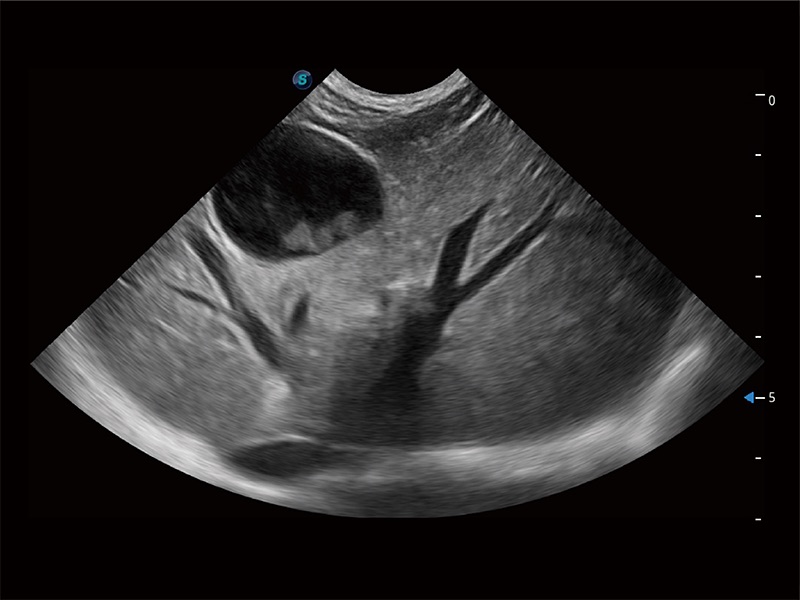

高性能和先进的临床应用工具可以为动物医生提供临床信心。ProPet 80 搭载了先进的腹部和浅表应用工具,帮助医生在日常临床实践中发挥前所未有的作用。

极大提升超低速微细血流的检出能力,同时更精准地滤除软组织和超声信号,为兽用医生提供以往无法通过常规血流获得的疾病诊断信息。

在传统二维血流成像的基础上,呈现血流的立体感,具有动感的生命力之美。即便是微小的血管也能轻松应对,提高了血流的视觉敏感性。

操作简便,无需高频度外力作用即可真实反映组织的形变,快速评估肿瘤良恶性。

非线性融合造影成像充分利用谐波和基波信号,为难以观察的血流进行增强显像。可用于线阵、凸阵、微凸阵、相控阵探头。